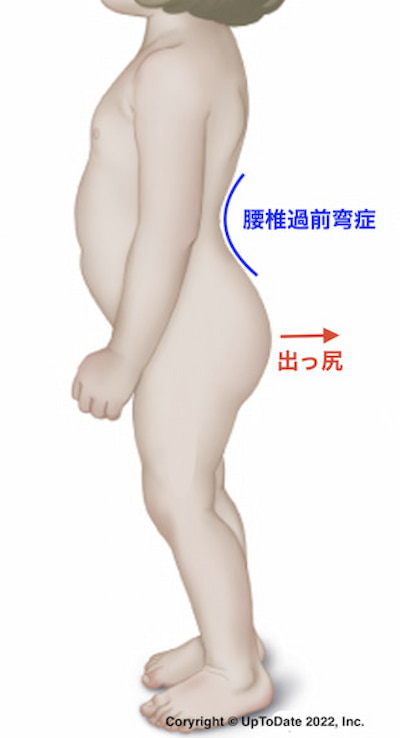

腰とお尻を横からみる

両側に脱臼がある場合、大腿骨頭が後方に脱臼するため、骨盤が前に傾いてしまいます。それを代償するために腰椎が弓なりになる(腰椎過前弯)ので、腰の部分が深く凹み、お尻が出っ張ります。

両側に脱臼がある場合、大腿骨頭が後方に脱臼するため、骨盤が前に傾いてしまいます。それを代償するために腰椎が弓なりになる(腰椎過前弯)ので、腰の部分が深く凹み、お尻が出っ張ります。